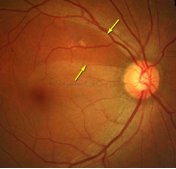

硬性渗出

硬性渗出样例,如箭头所示。其他区域视网膜上更深位置的较暗的黄白色小点是玻璃膜疣,不是硬性渗出。

硬性渗出(HE)是视网膜上的小的白色或黄白色、边界清晰的的沉着物。通常呈现为“蜡状”,闪亮或有光泽。

硬性渗出通常位于视网膜外层,但可能会更偏表面,尤其是在视网膜水肿存在的情况下。硬性渗出可以是独立的小点,也可以是连续的片状斑点,或围绕在视网膜水肿或微血管瘤周围的呈环状病变。在局部视网膜增厚的区域内,融合的硬性渗出可出现在视网膜外层或视网膜下。

注意:硬性渗出(HE)须与玻璃膜疣(一种常见的年龄相关性病理改变)相区分。